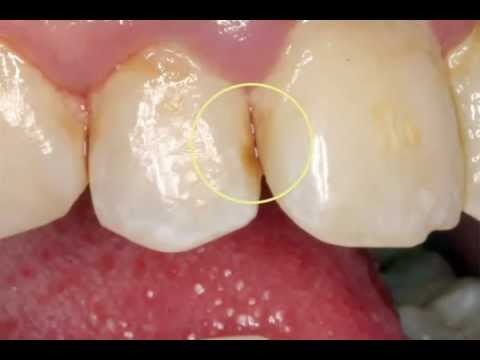

home Health Concerns Tooth Decay – How to Avoid It Tooth Decay – How to Avoid It By dentists Posted in Health Concerns Posted on June 11, 2017